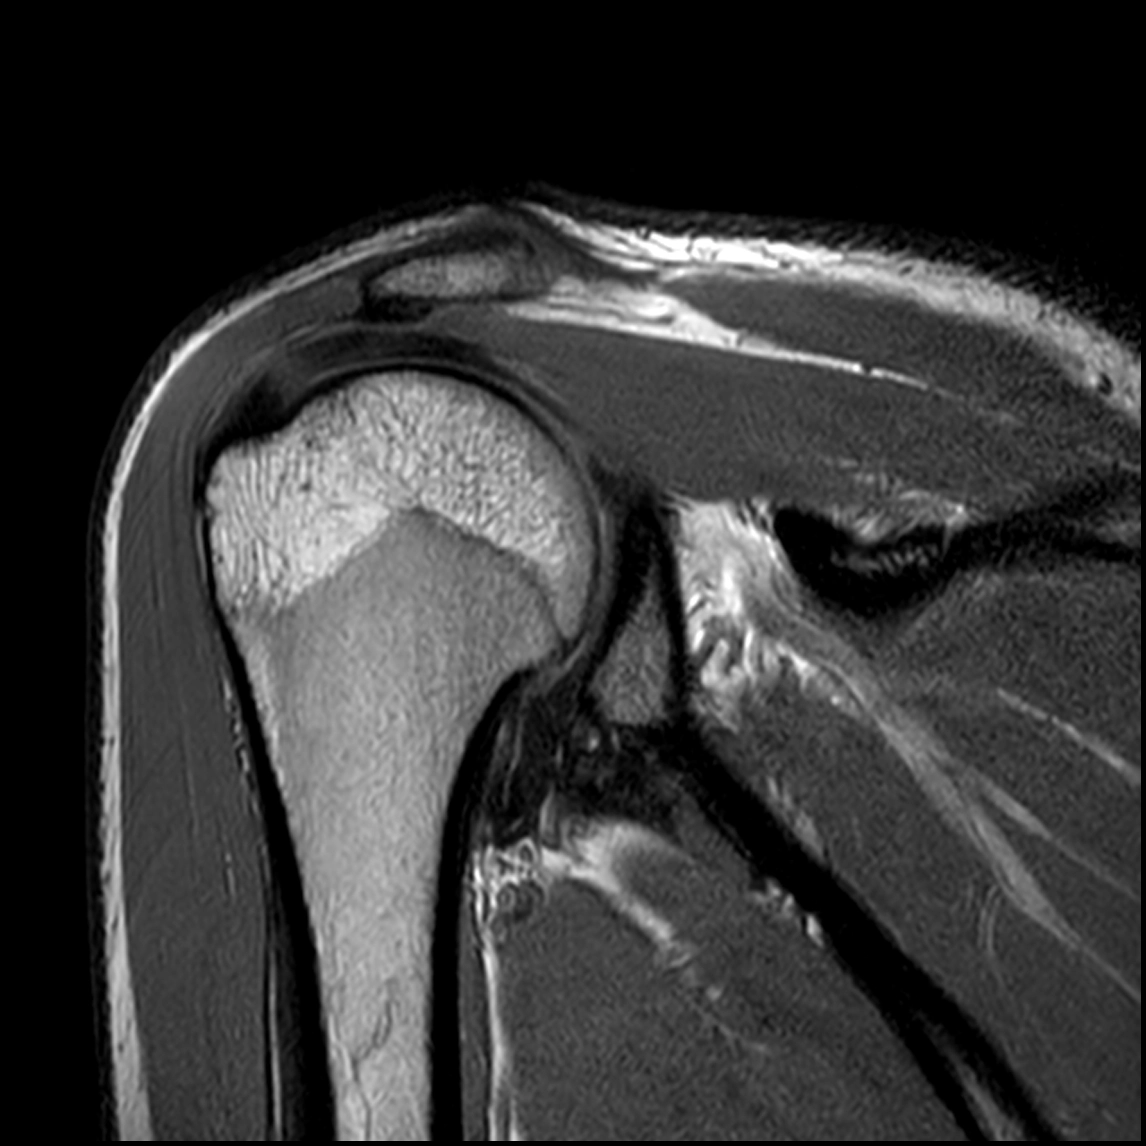

Resonancia magnética:

Examen no invasivo de mayor calidad de imagen y mayor precisión para detectar lesiones. Si se complementa con contraste intraarticular mejora de gran manera la exactitud de los hallazgos.